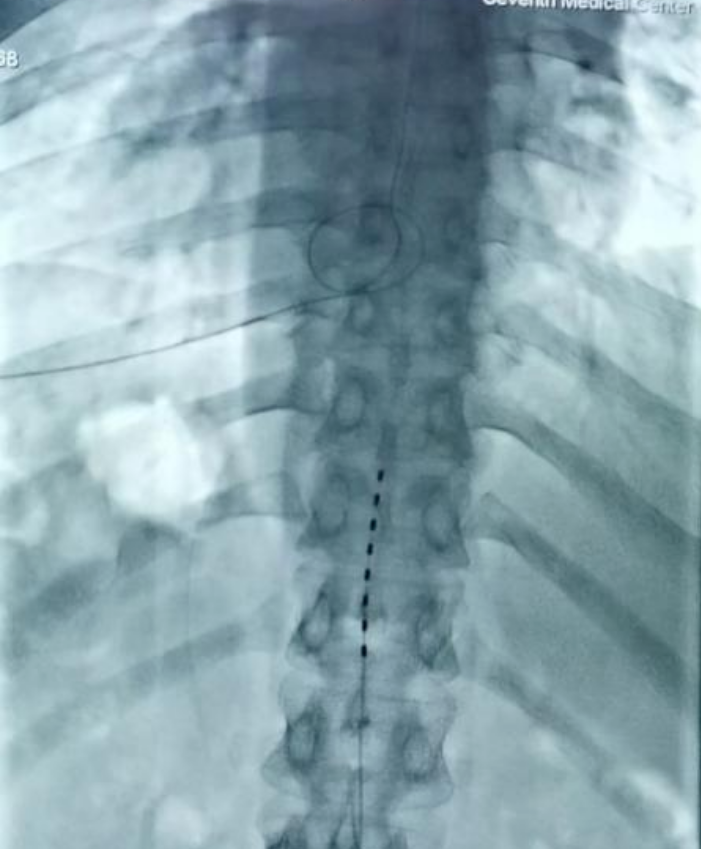

夏主任及其團隊對患者的病情進行了詳細的評估,并與患者及家屬充分溝通后,決定實施脊髓電刺激植入術(shù)。在術(shù)中電生理和術(shù)中影像的引導下,通過穿刺的技術(shù)將1根柱狀電極精準放置于T11-T12節(jié)段中線位置。